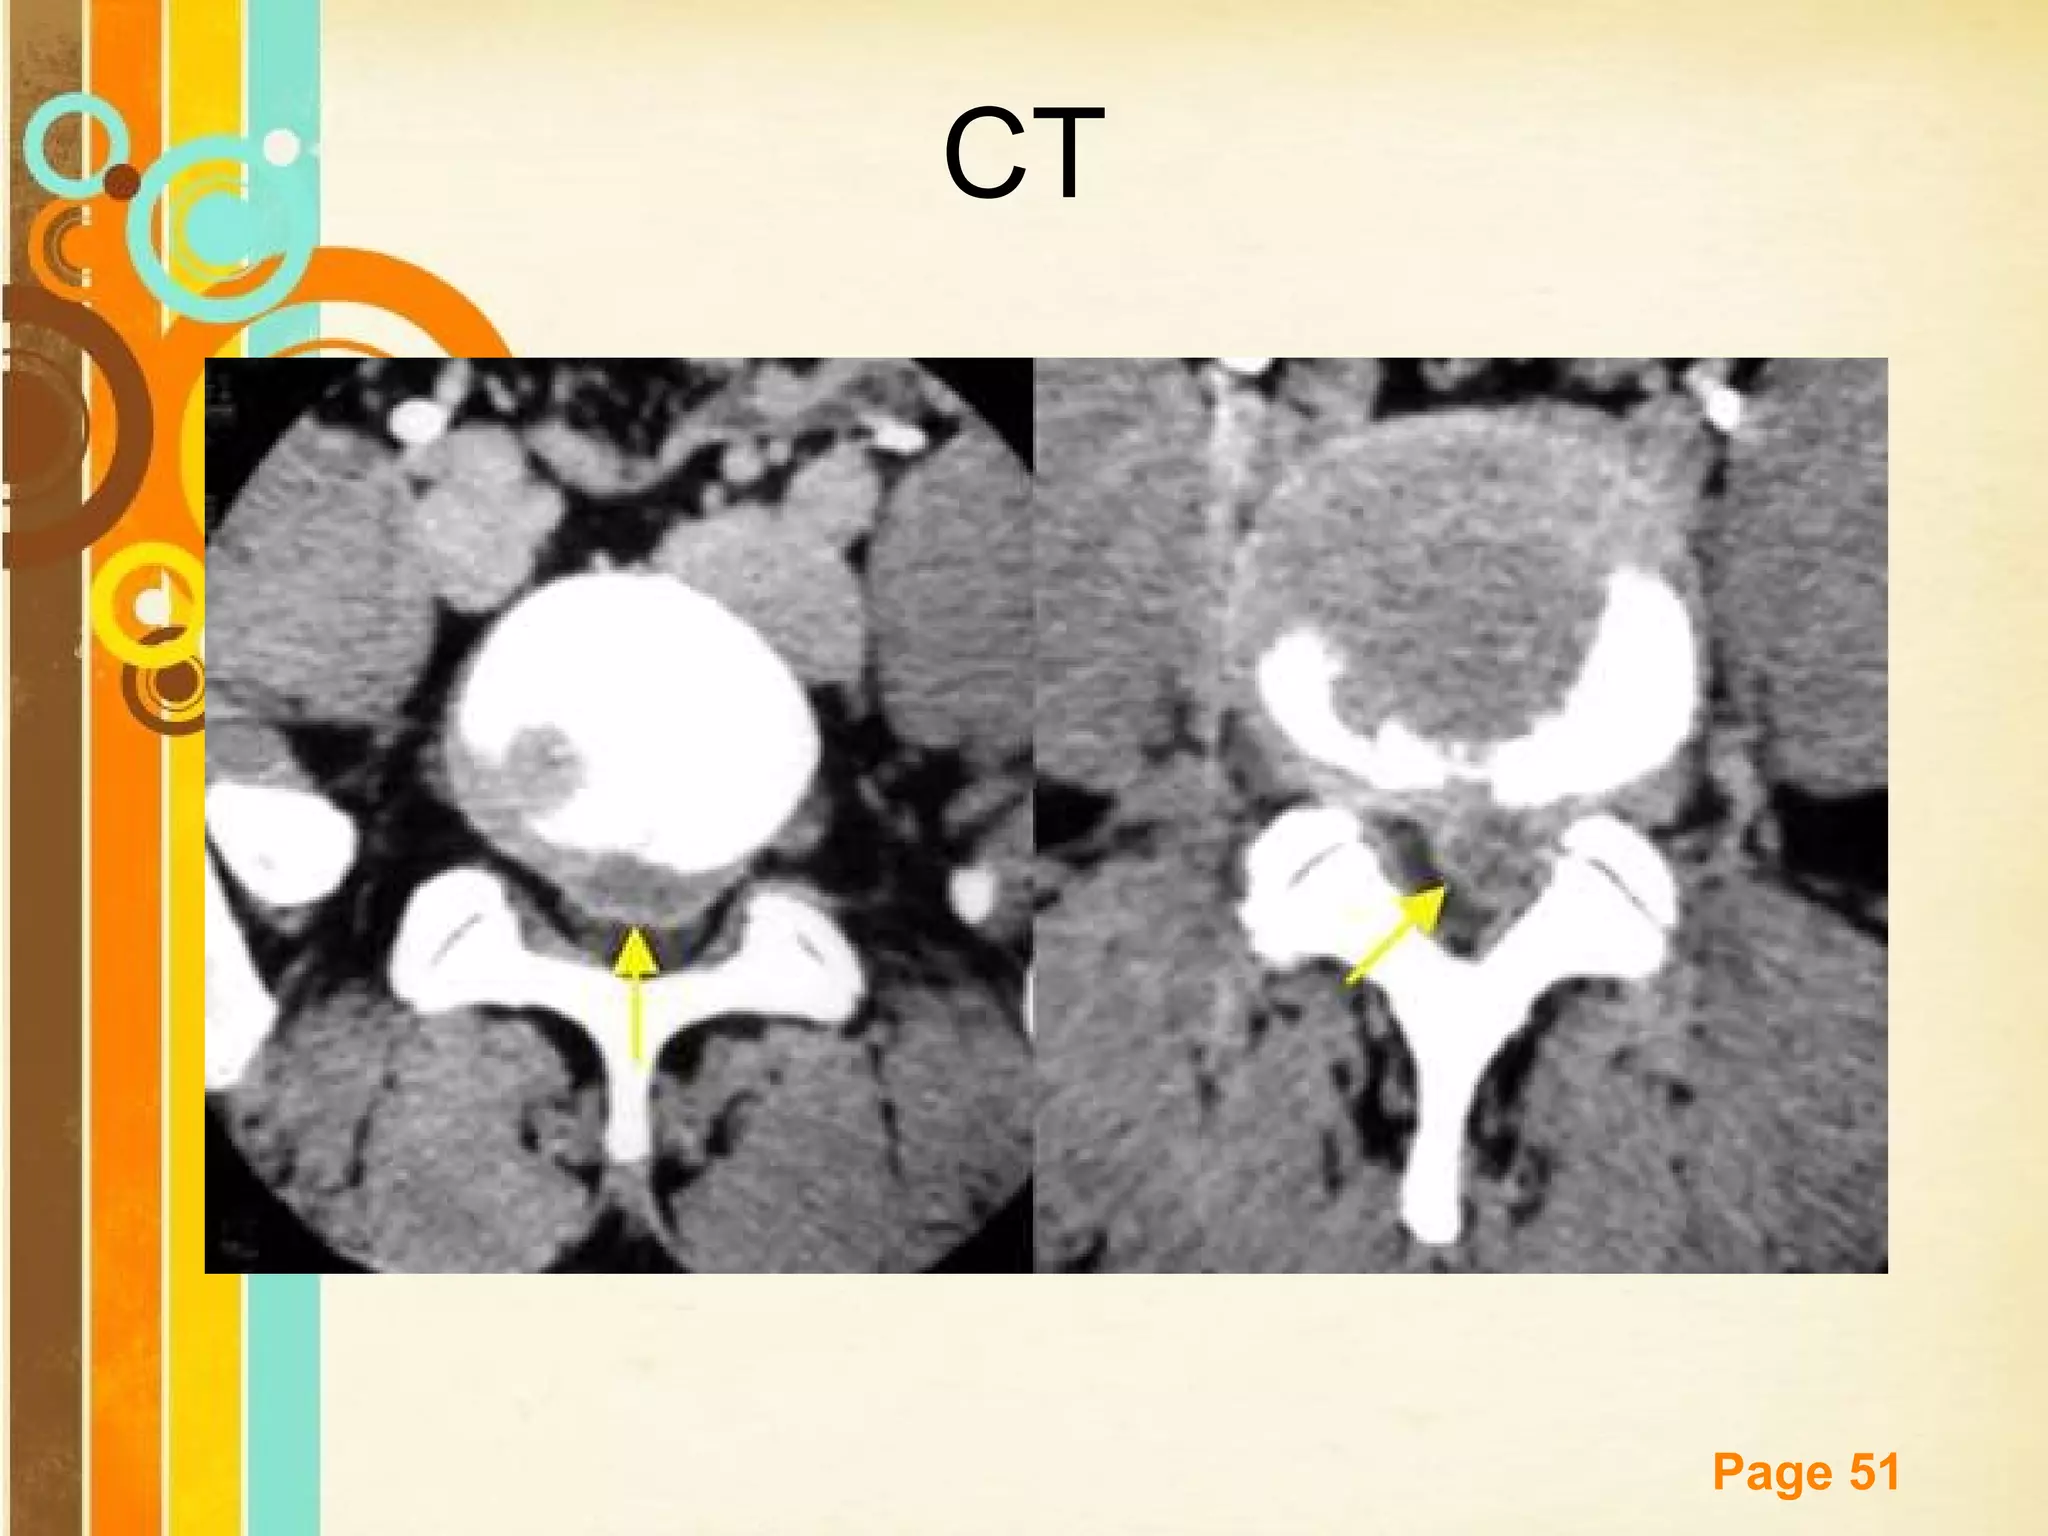

CT

Sagittal CT reconstruction

Spondylolisthesis. Axial CT image

spinal canal at this level